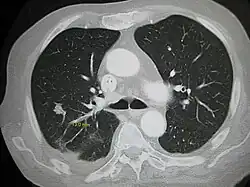

Da es anfangs an Symptomen mangelt, werden Lungenmetastasen oft beim Thorax-Röntgen im Rahmen von Nachsorgeuntersuchungen gefunden. Lungenmetastasen zeigen sich im Allgemeinen als Rundherde im Bereich des Lungenmantels, können aber auch zentral innerhalb der Bronchien wachsen und in umliegende Lymphknoten streuen.[2]

Die wichtigsten diagnostischen Instrumente sind die Röntgenaufnahme der Lunge in 2 Ebenen (Darstellung von Rundherden ab einem Durchmesser von 1 cm), die Computertomographie der Lunge mit oder auch ohne Gabe von Kontrastmittel und im Zweifelsfall auch eine Punktion des Metastasengewebes.[2]